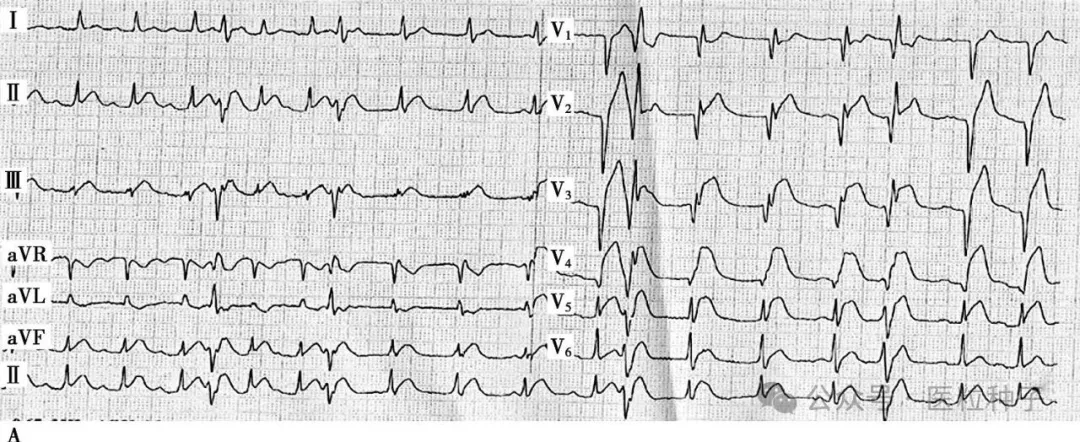

患者男性,34岁,主因胸闷憋气3周余于2015年12月22日入院。患者于2015年11月25日午餐后突然出现胸骨后憋闷、疼痛,呈压榨性,伴烦躁、大汗、恐惧,症状持续不能缓解,急诊至当地县医院,心电图提示:V2~V5导联ST段弓背向上抬高,诊断为“急性前壁心肌梗死”,给予阿司匹林300mg、氯吡格雷片600mg顿服,即刻向上级医院转诊;11月25日15点52分转入当地市医院,测血压70/40mmHg,给予多巴胺泵入,急查心肌酶升高,心电图提示:Ⅱ、Ⅲ、aVF及V2~V5导联ST段弓背向上抬高,诊断为“急性下壁、前壁心肌梗死”,于当日17时行急诊PCI手术,冠脉造影(图1)提示:左优势型,LAD开口完全闭塞,LCX粗大,远段完全闭塞,RCA未见明显狭窄,术中出现心源性休克,给予植入IABP支持,并给予LAD球囊扩张+血栓抽吸,LAD前向血流恢复TIMI 3级。术后常规抗凝、抗血小板治疗,血压稳定后给予拔除IABP(具体不详)。患者自觉症状未见好转,仍有胸闷,憋气,体力明显受限。

图1 当地心电图及急诊PCI结果

A.当地市医院急诊心电图提示:Ⅱ、Ⅲ、aVF、V2~V5导联ST段弓背向上抬高;B.急诊造影提示:LAD开口闭塞,回旋支远段栓塞;C.PCI术后,LAD TIMI 2级,LCX远段血流未恢复